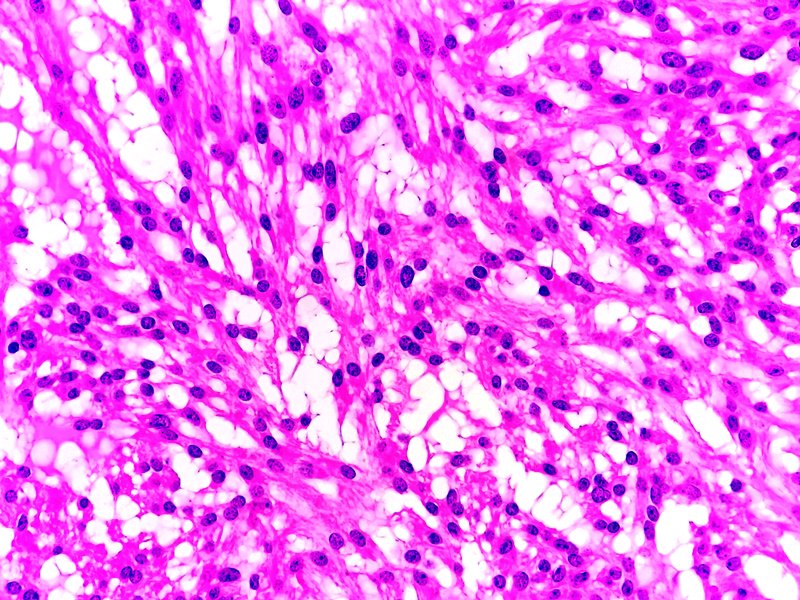

Próstata. Tumor estromal de potencial maligno incierto. Tinción HE.

Anapat tweet mediaAnapat tweet mediaAnapat tweet media